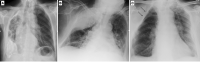

Fig. 17

Chest X-ray shows diffuse calcified pleural plaques on the right hemithorax due to the presence of extensive and coarse unilateral calcified pleural thickening (fibrothorax) (A). Chest X-ray shows an extensive opacity of the right upper lung with smooth internal margins and an obtuse angle with the lateral chest wall due to the sequelae of an extra-pleural artificial pneumothorax (B). Chest X-ray of an 83-year-old female shows multiple ribs resection following surgical treatment of TB (thoracoplasty) (C)